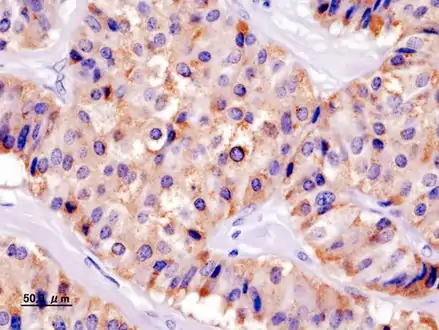

Pathology of pancreatic endocrine tumour (insulinoma).